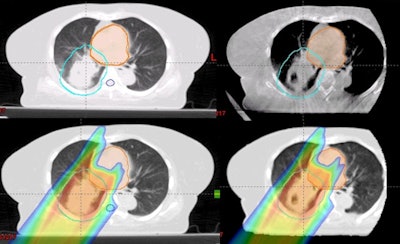

Top row (left to right): The planning CT and CBCT. Bottom row: The dose distribution on the planning CT, and on the virtual CT generated from the CBCT. Images courtesy of Boon-Keng Teo, PhD.Tumor enlargement or lung collapse, for example, can result in a shortened beam penetration, reducing coverage of the target. In contrast, tumor shrinkage can result in the radiation beam penetrating further than intended, damaging regular tissues. To compensate for this, regular CT scans are taken during the course of treatment to identify anatomical changes and adjust the therapy accordingly.

In their new study, Boon-Keng Teo, PhD, a radiation oncologist at the University of Pennsylvania, and colleagues, has developed a CBCT-based workflow for adaptive proton therapy. First, prior to each individual proton treatment, patients are given a CBCT scan. From this, a virtual CT scan is generated by deforming the treatment's original planning CT scan onto the geometry of the current CBCT scan.

From this, a fast, range-corrected dose distribution of the intended treatment is calculated. If the identified dosimetric changes are found to be within safe limits, treatment may proceed -- else, an offline review of the virtual CT is called for, which may lead to a replan CT to adjust the treatment accordingly.